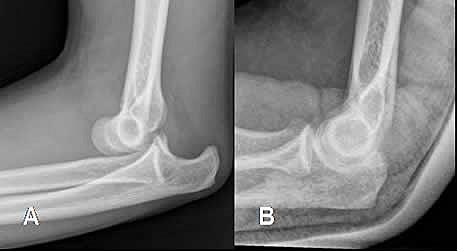

• Mi Codo Dislocado :0

Mi Codo Dislocado :0

Ese día estaba jugando futbol con mis vecinos, yo era portero y el balón ya había salido, me agaché por el balón, justo cuando lo tenía en las manos, se barren en mí, yo solo vi que di una voltereta y terminé como a un metro de distancia de donde estaba y al ver si todo estaba bien en mí me dí cuenta que mi codo no estaba en su lugar, empecé a llorar de la desesperación y me llevaron a urgencias al ISSTEP me acomodaron el codo a la mexicana, sin anestesia, tuve el yeso por unos meses